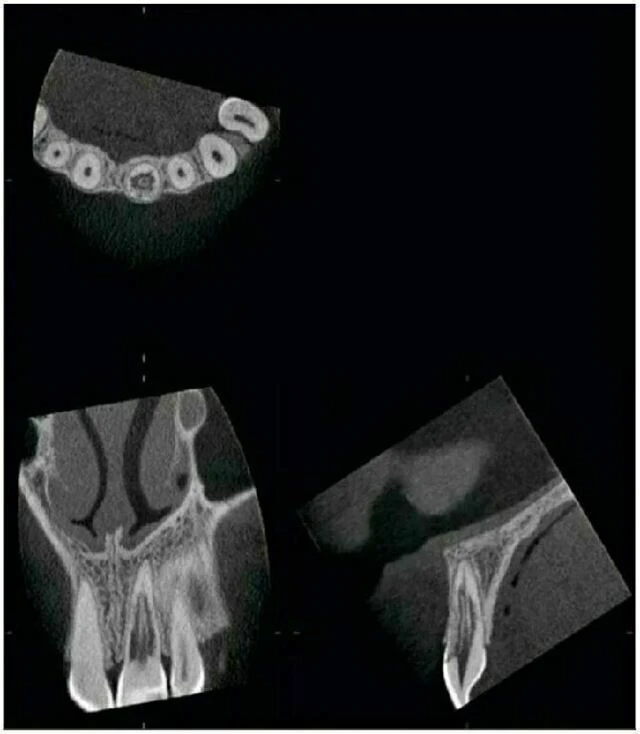

Chụp kiểm tra bằng Accuitomo vùng răng hàm trên phía trước cho thấy răng cửa giữa hàm trên bên phải có một ống tuỷ rất rộng. Điều này có thể thấy ở răng bị chết tuỷ từ khi tuổi còn nhỏ. Tại chóp răng này, thấy có một nang lớn. Bờ của nó không rõ và xương xung quanh đặc hơn bình thường. Tổn thương vì vậy có hình ảnh của một nang nhiễm trùng quanh chóp. Kiểm tra còn cho thấy một đường nứt ở phần chóp của răng cửa giữa bên phải.

Ở răng cửa giữa bên trái, thấy một đường gãy hầu như nằm ngang qua chân răng. Mảnh gãy phía chóp và phía thân răng, tuỷ răng hầu như bị hoại tử sạch.